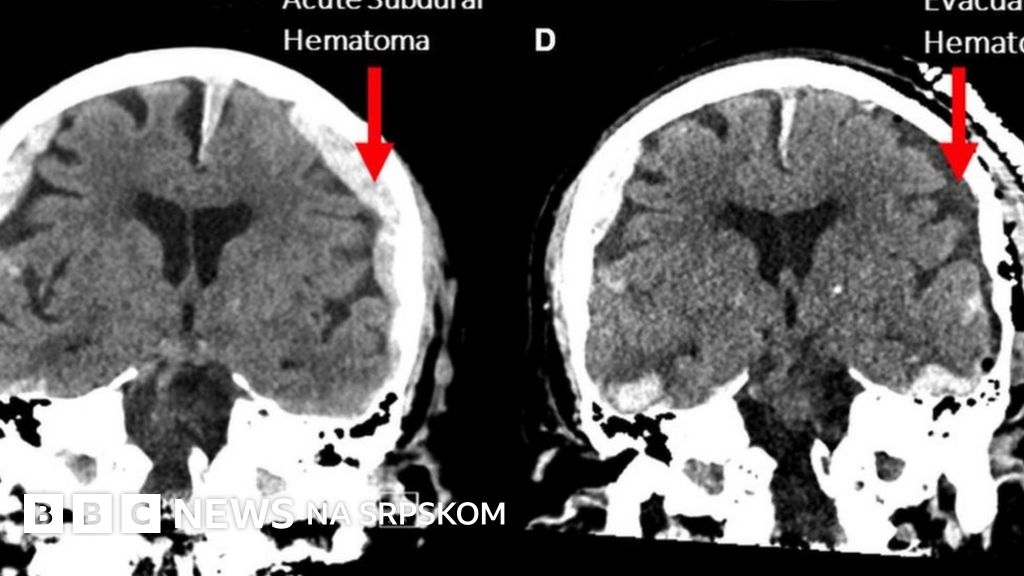

Činjenica da je pacijent imao epilepsiju, da mu je mozak bio oteknut i da je krvavio, dodatno komplikuje situaciju.